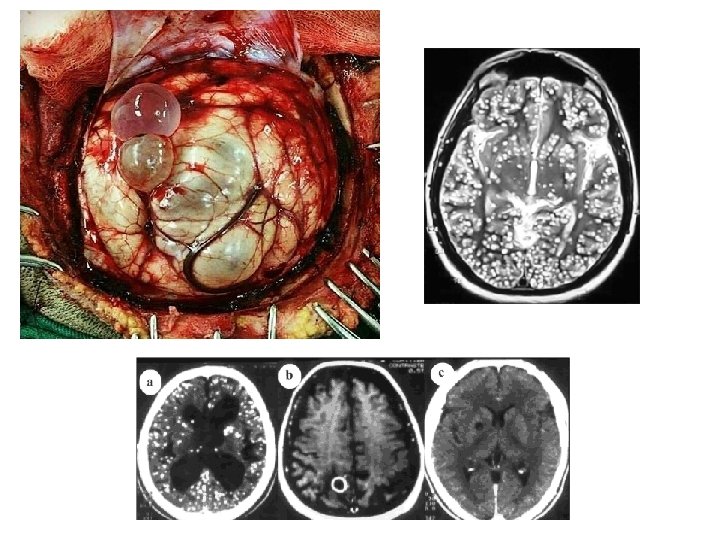

CISTICERCOSE

CAUSADOR Larva cisticerco de Taenia solium.

TRANSMISSÃO Através da ingestão de ovos de Taenia solium presentes na água e/ou nos alimentos. Obs: O homem faz o papel do porco, o hospedeiro intermediário.

SINTOMAS § Larvas no cérebro (Neurocisticersose) - Dores de cabeça; Ataques epilépticos; Convulsões; Vômitos; Crises de fúria e irritação.

SINTOMAS § Larvas nos músculos - Dores musculares;

SINTOMAS § Larvas nos olhos - Dores; - Deficiência visual; - Cegueira;